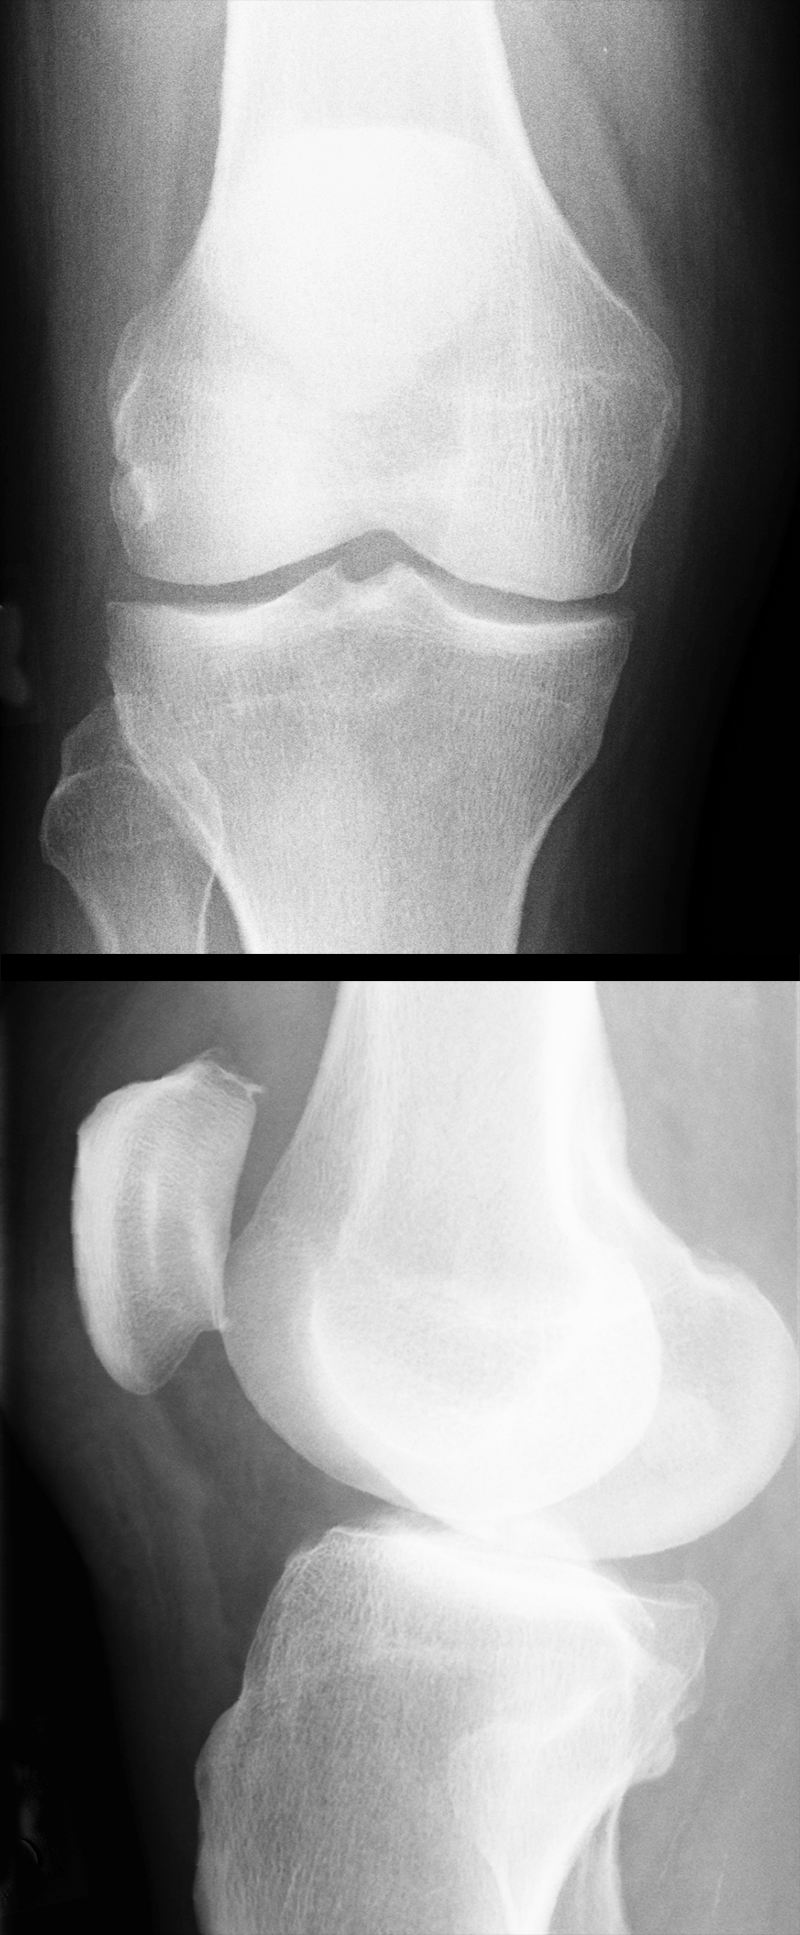

RÖNTGEN – normales Kniegelenk (groß)

normal